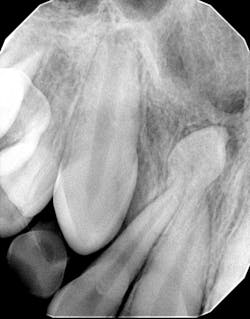

My hygienist had taken radiographs prior to me coming in.

Diagnosis: Mesiodens tooth

- Diagnosis is primarily via radiograph and can be confirmed by taking multiple angles using intraoral and extraoral radiographs (i.e., panoramic, periapicals, etc.). Furthermore, three-dimensional CBCT scans allow dialing in on the palatal location of the mesiodentes and their relationship to adjacent teeth. Delayed or altered eruptions of adult dentition also give rise to the suspicion of mesiodentes. Other common signs include cyst formation and crowding.